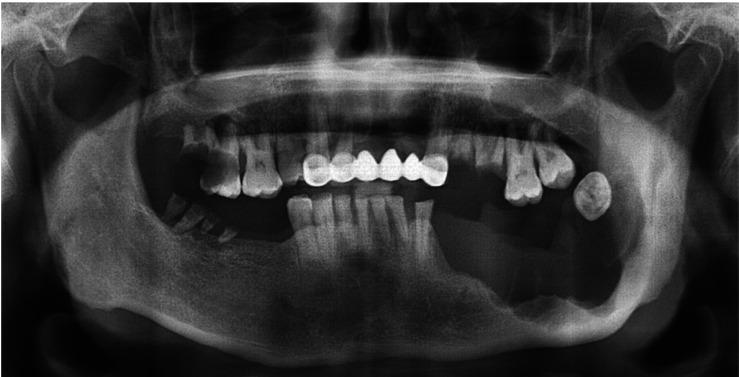

Ameloblastic carcinoma is a rare odontogenic malignant tumor with the histologic features of both ameloblastoma and carcinoma. It occurs more frequently in the mandible than in the maxilla and it may appear or develop from a preexisting ameloblastoma or odontogenic cyst. Rapidly progressing, painful swelling is the most common symptom, and radiographically, it shows significant bone resorption and cortical perforation. This report described a case of ameloblastic carcinoma in a 45-year-old man who presented with swelling in the left mandible. The lesion showed combined features of benign findings, such as an expansile cortex with a distinct border, and malignant findings, such as a large exophytic mass with frank bone resorption. Excisional biopsy was performed and a final diagnosis of ameloblastic carcinoma was made.

成釉细胞癌是一种罕见的牙源性恶性肿瘤,具有成釉细胞瘤和癌的组织学特征。它在下颌骨比在上颌骨更常见,可能表现为或由先前存在的成釉细胞瘤或牙源性囊肿发展而来。快速进展的疼痛性肿胀是最常见的症状,在影像学上,它表现出明显的骨质吸收和皮质穿孔。本报告描述了一例45岁男性成釉细胞癌病例,该患者左下颌骨出现肿胀。病变显示出良性表现(如边界清晰的膨胀性皮质)和恶性表现(如伴有明显骨质吸收的大的外生性肿块)的综合特征。进行了切除活检,最终诊断为成釉细胞癌。